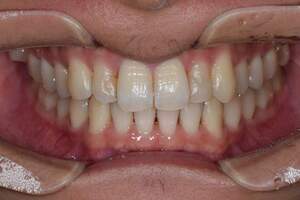

歯石除去

治療前

治療後

| 年齢 | 25歳・男性 |

| 主訴 | 歯石をとりたい・検診 |

| 治療内容 | 各種検査・歯石除去 |

| 治療期間 | 60分 |

| 費用 | 初診料3,000〜4,000円前後 +歯石除去約1,000円 |

| リスク・副作用 | ・処置後に歯がしみることがあります。 ・歯と歯の間に隙間ができるので、息が漏れ発音しにくいと感じることがあります。 ・歯ぐきの炎症が軽減すると歯ぐきが引き締まり、歯が長く見えることがあります。 |

| 担当者所見 | 前歯の裏側にすぐに歯石が溜まってしまいザラザラして気になるとご相談いただいたので適切な歯ブラシの当て方とフロスの通し方をお伝えさせて頂きました。 |